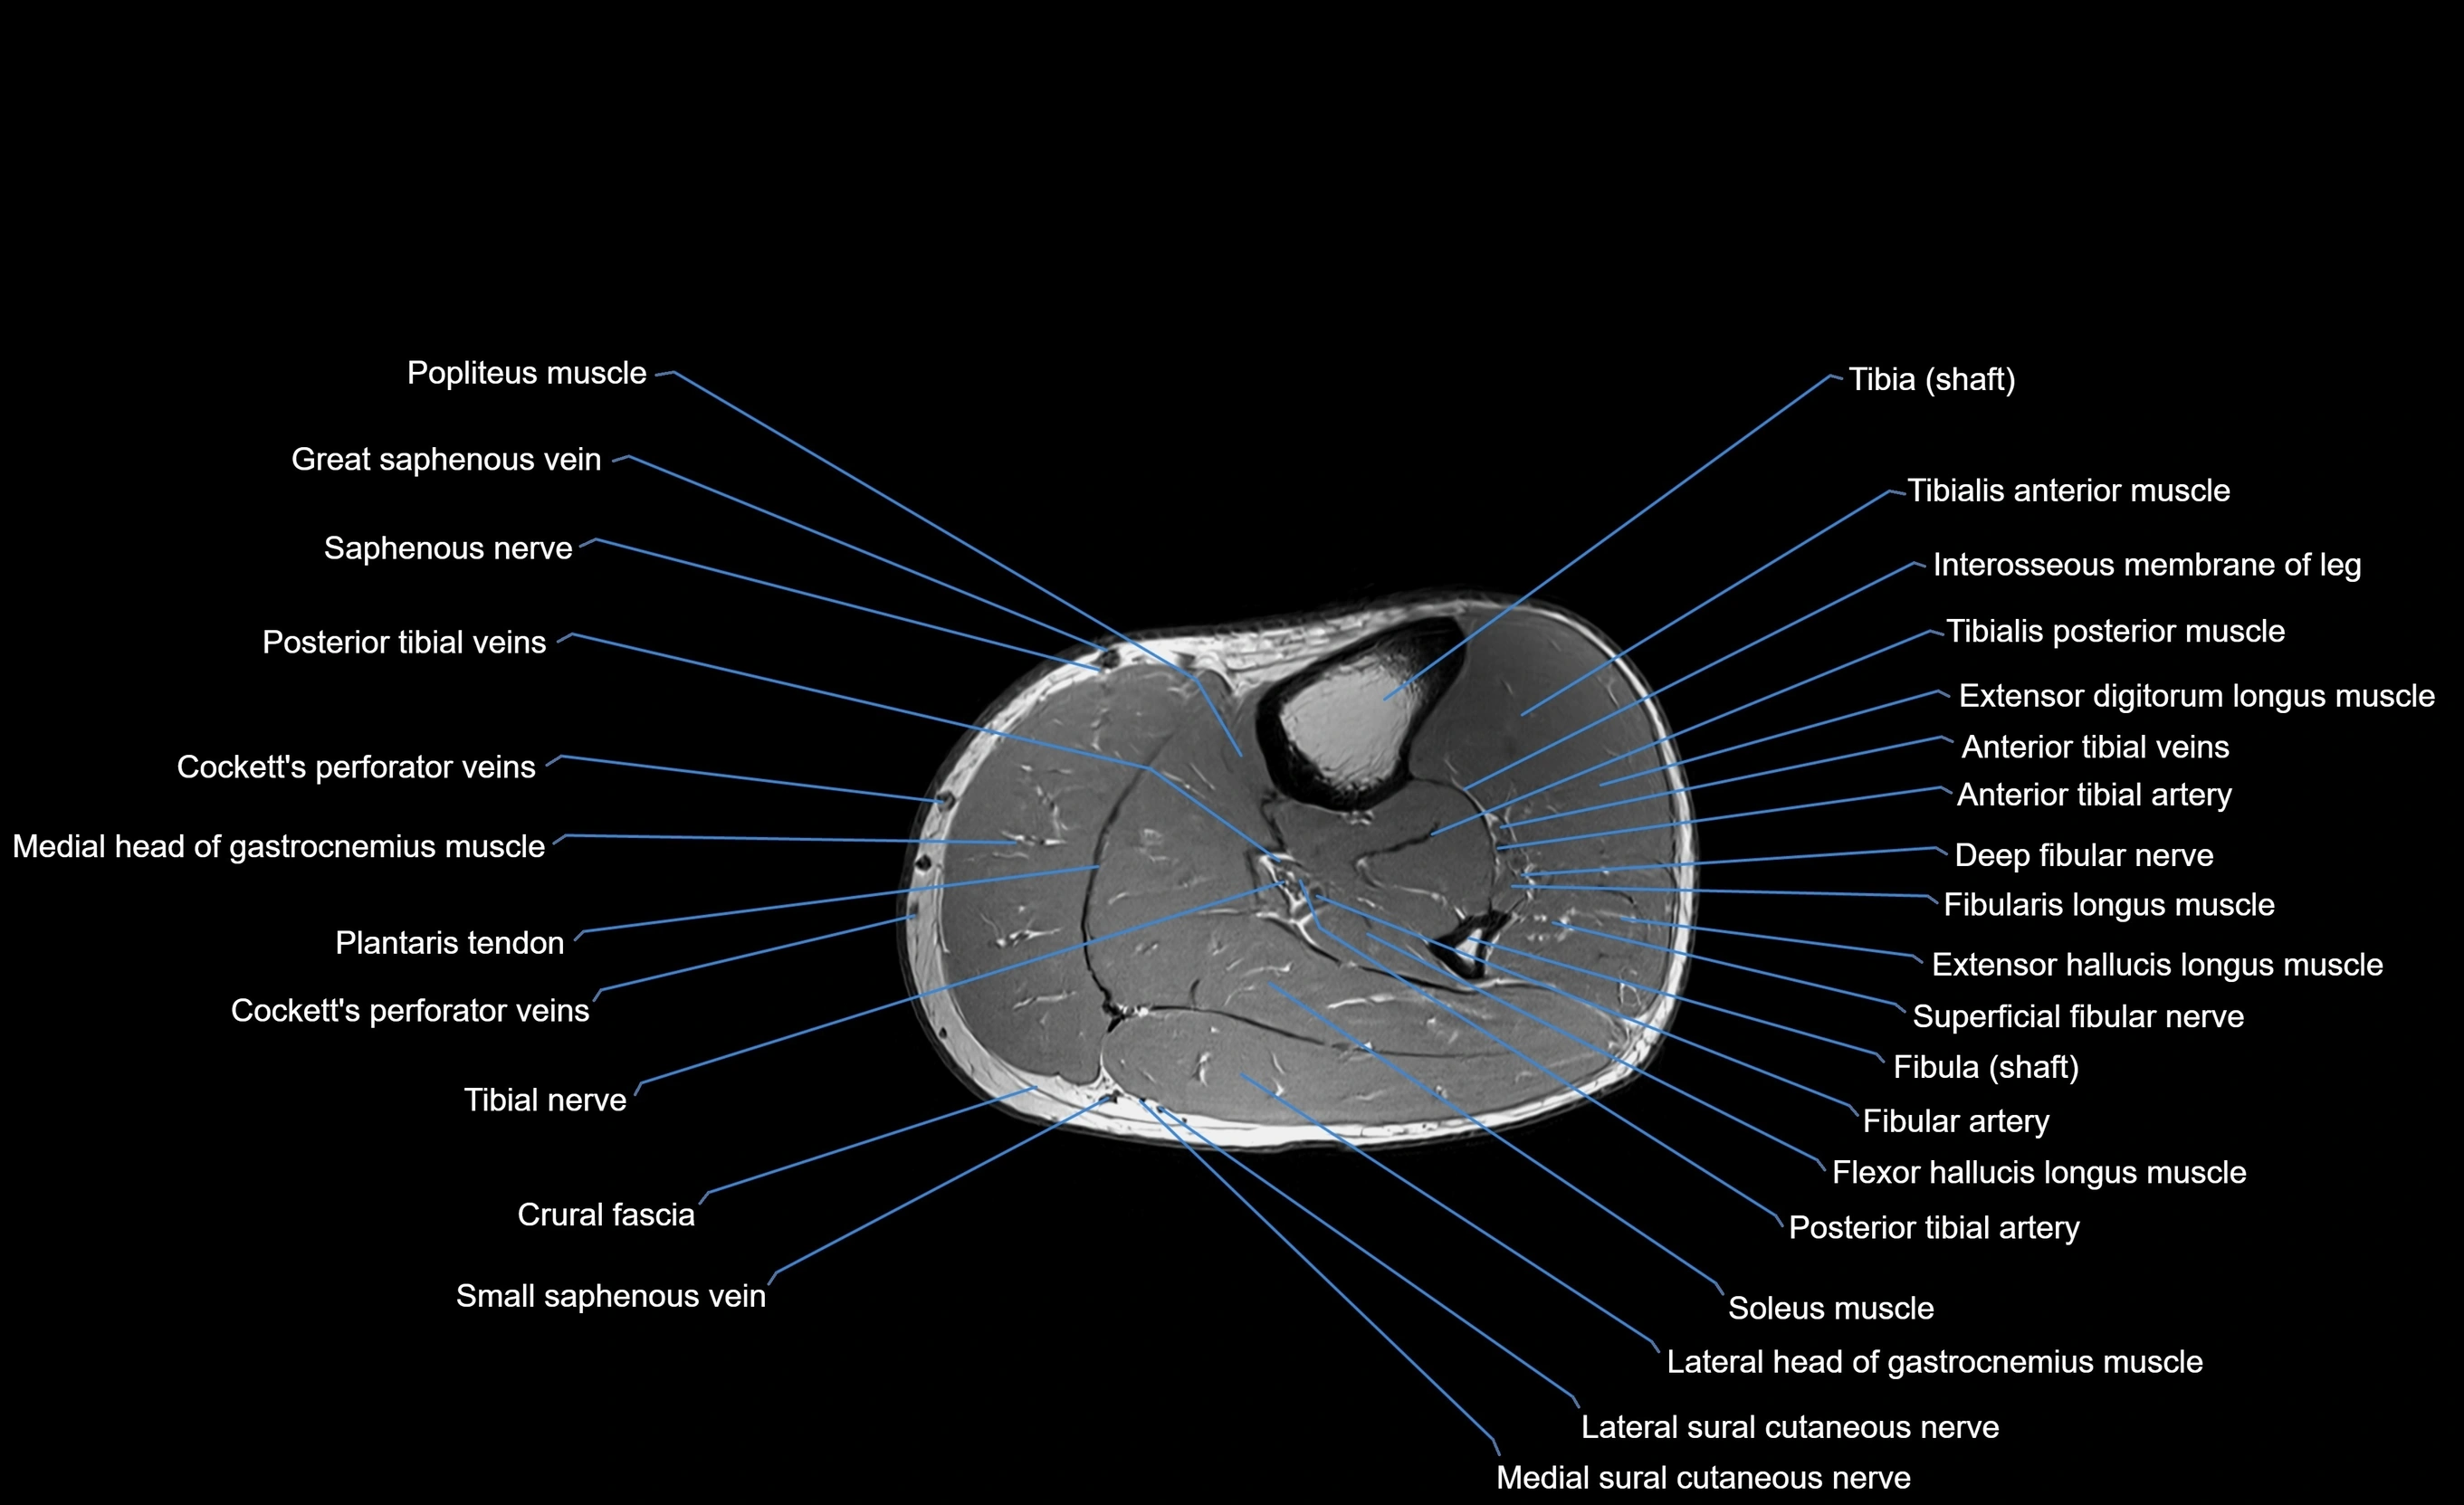

MRI image